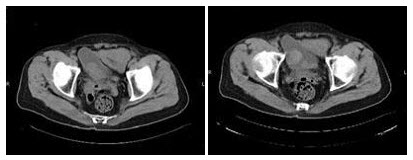

142、单项选择题

女,57岁,咳嗽,胸闷,胸痛2月余,5年前被确诊为子宫绒毛膜癌,结合影像学检查,最可能的诊断是()

A.肺癌

B.肺结核

C.肺转移瘤

D.结节病

E.矽肺

143、单项选择题 碘过敏试验最可靠的方法是()